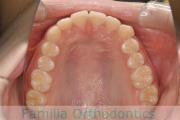

上の前歯の並びが気になるのできれいにしたい、ということで来院されました。マウスピース型矯正装置のひとつ、インビザライン/InvisalignR(薬機法および医薬品副作用被害救済制度の対象外)を用いて治療しました。

非抜歯で2年弱、20回程度の通院で治療が完了しました。

マウスピース矯正は、患者さんの協力に治療結果が左右されるところはリスクと言えるかもしれません。